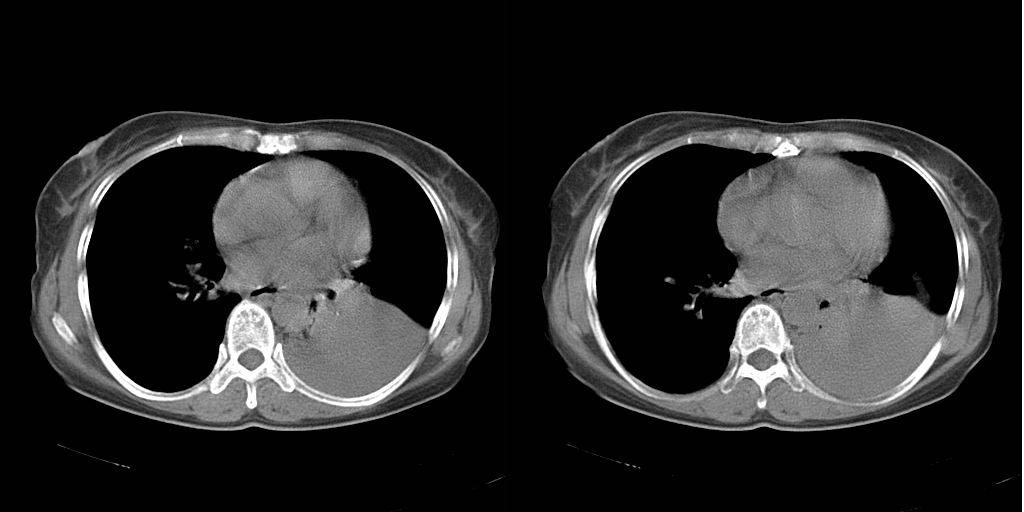

以下是引用dyqct在2007-1-23 15:01:00的发言:[br]左肺下叶实变、略萎陷,近肺门下部密度不均。上腔静脉后及隆突前见肿大淋巴结。余未见异常。[br]考虑:1、左肺下叶中心型肺癌伴肺不张、纵隔淋巴结转移;[br] 2、建议增强扫描并做任意平面重建确定肿块范围及支气管受累情况。

以下是引用同在2007-1-23 19:59:00的发言:[br]左肺下叶中央型肺癌伴肺不张及纵隔淋巴结转移.